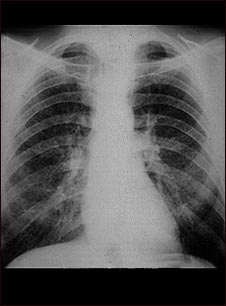

Pulmones de un trabajador del carbón; rayos X

Esta radiografía de tórax muestra los pulmones de un minero. A ambos lados de los pulmones hay áreas difusas, pequeñas (de 1 a 3 mm. cada una) y claras. Las enfermedades que pueden explicar estos hallazgos en una radiografía son la neumoconiosis del minero (NCM) etapa I, silicosis simple, tuberculosis miliar, histiocitosis X (granuloma eosinofílico) y otras enfermedades pulmonares infiltrativas difusas.